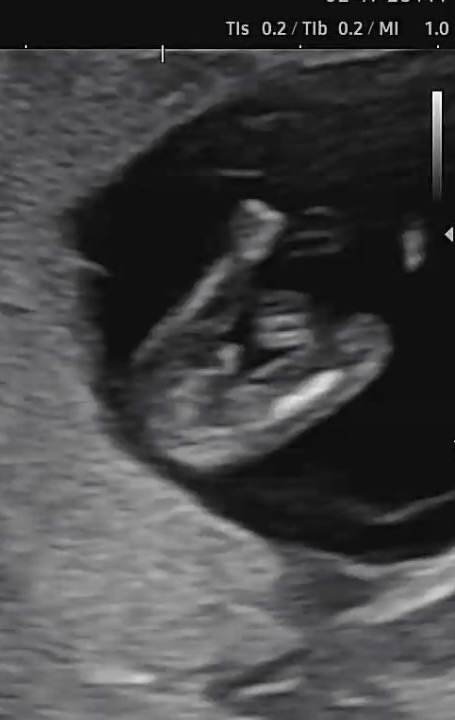

11주 5일 아들이 맞나요🤣

아직 시기가 이른건 알지만 초음파에 이정도로 보이면 아들겠죠?ㅎㅎㅎ